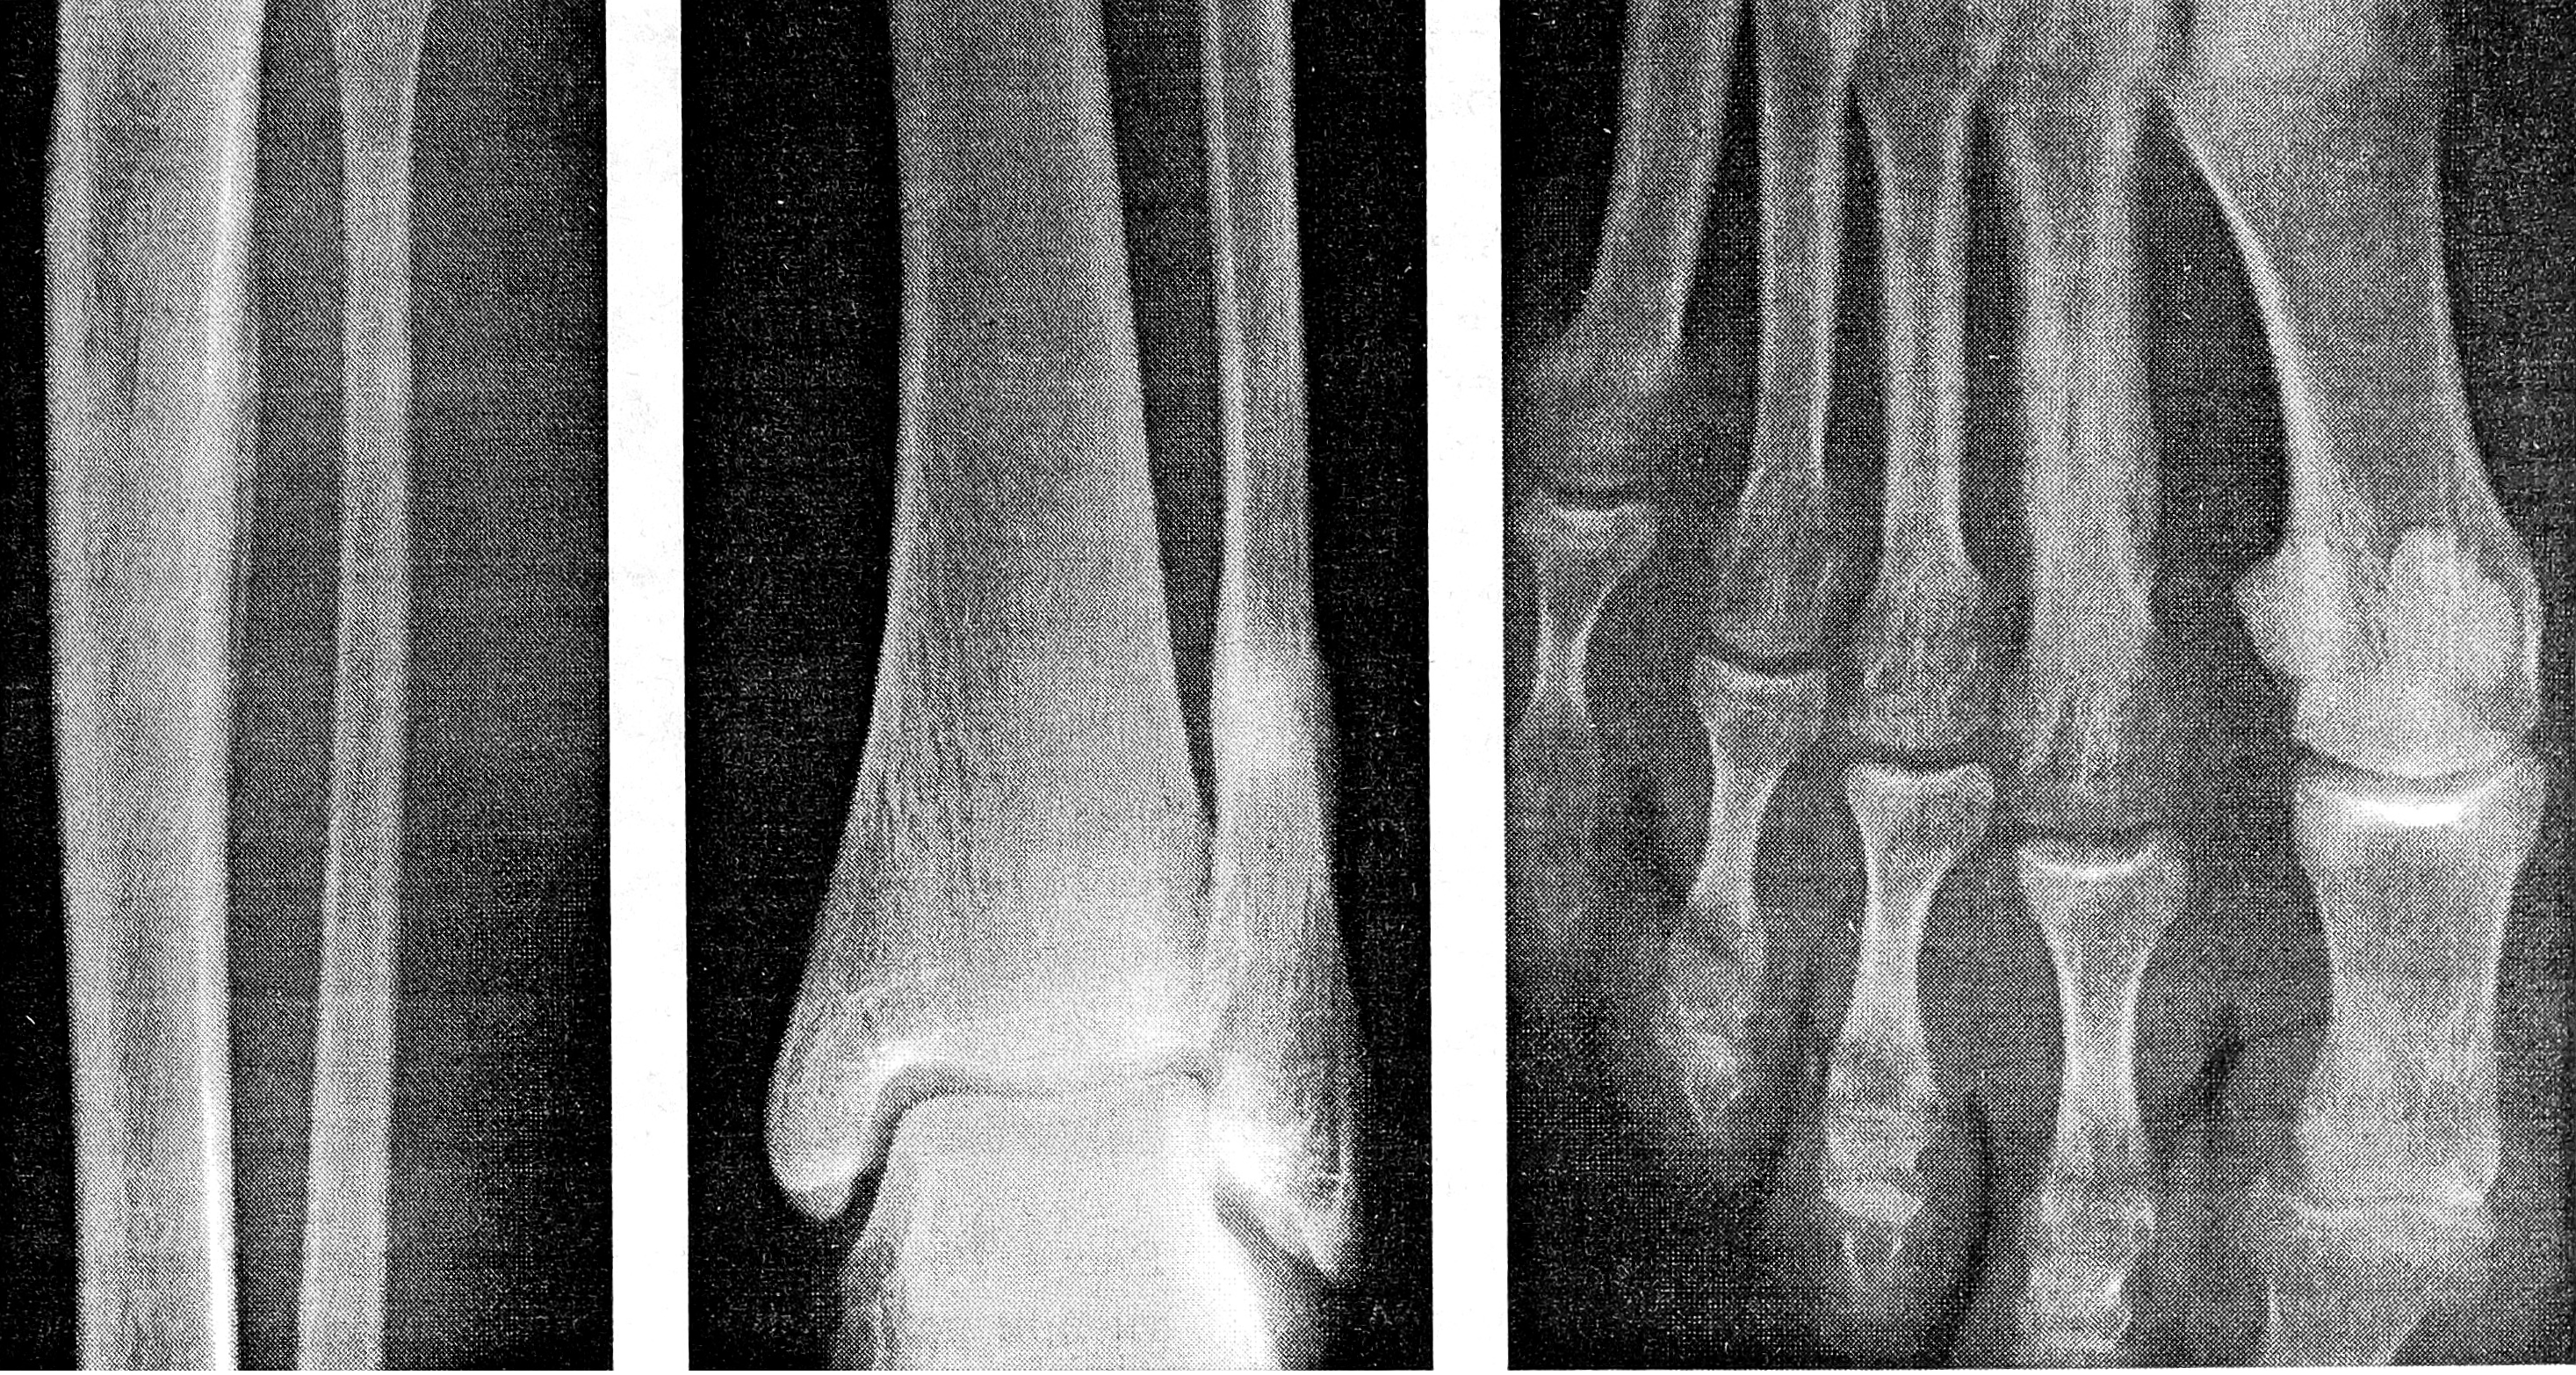

Рис. 2. Гиперостоз от перенапряжения: рентгенограммы локтевой кости до (а), через 130 (б) и 845 (в) сут функциональной перегрузки.

В первые 1—1,5 мес функциональной перегрузки происходит быстрое увеличение толщины самого тонкого участка диафиза локтевой кости. Со 2-го месяца это увеличение замедляется за счет физиологической перестройки и распространяется на всю кость (рис. 2).

Рис. 6-8

Рис. 6. Периостальная реакция на перенапряжение большеберцовой кости правой голени у ребенка 4 лет (1,5 мес от начала заболевания).

Рис. 7. Полоса просветления, окруженная зоной склероза, в дистальной трети диафиза малоберцовой кости. Ограниченные периостальные наслоения (голень женщины 57 лет, длительность заболевания 7 мес).

Рис. 8. Гиперостоз от перенапряжения II плюсневой кости у женщины 36 лет (1,5 года от начала заболевания).